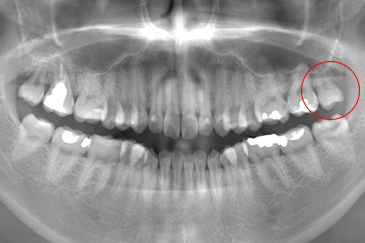

CASE 2

抜歯前

抜歯後

基本情報

| 年齢・性別 | 20代・女性 |

|---|---|

| 主訴 | 左上の親知らずが抜きたい 左上8番 |

| 治療内容 | 通常抜歯 |

| 治療期間 | 約15分 |

| 治療費 | 約3,000円 |

| リスク・副作用 | 2〜3日は腫れと痛みがある。 |